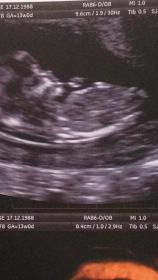

The skull theory and nub theory are making me confused Attachment 31520

Boy???

I'd guess boy

Boy

I don't think I can see the nub, sorry.